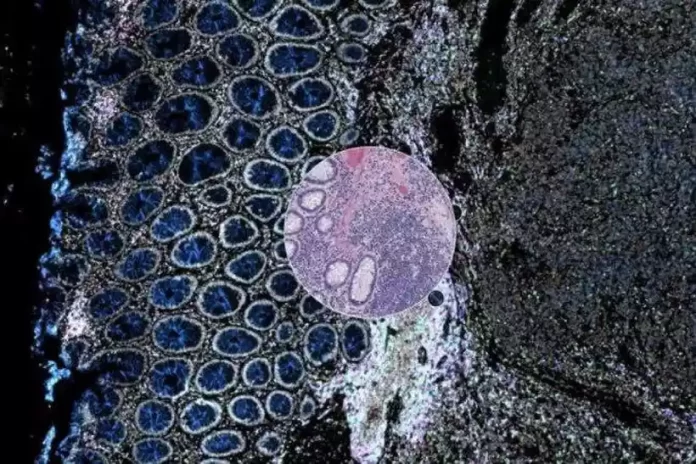

O artigo descreve a Orion como uma plataforma de imagens digitais que integra informações obtidas por meio da histologia tradicional, ramo da ciência que estuda os tecidos, com detalhes revelados por imagens moleculares em uma amostra de tumor. Com ela, pode-se identificar uma área de interesse na amostra do câncer com base em detalhes moleculares obtidos por imagens de imunofluorescência e, assim, identificar marcadores biológicos da doença. Esses biomarcadores se enquadram em duas categorias: prognóstico, que ajudam a prever quais pacientes se sairão bem ou mal; e preditivo, que indicam quem vai responder a um determinado medicamento.

Nos testes, os pesquisadores usaram Orion em amostras de tumores de 74 pacientes com câncer colorretal. A equipe observou que as informações obtidas pela nova ferramenta permitiram identificar um biomarcador de resultado ou uma combinação específica de recursos que previam em quais voluntários a doença provavelmente progrediria e em quais, não.

Segundo os autores, um biomarcador normalmente determina quantos e quais tipos de células estão presentes em diferentes partes de uma amostra, incluindo as de defesa. No ensaio, Orion identificou um biomarcador baseado na presença de células T marcadas com proteínas específicas, CD4 ou CD45, e células tumorais que continham as proteínas PD-L1 ou SMA. Esses e outros biomarcadores tiveram um desempenho tão bom ou melhor do que um teste clínico chamado Immunoscore, usado por oncologistas para avaliar câncer colorretal.